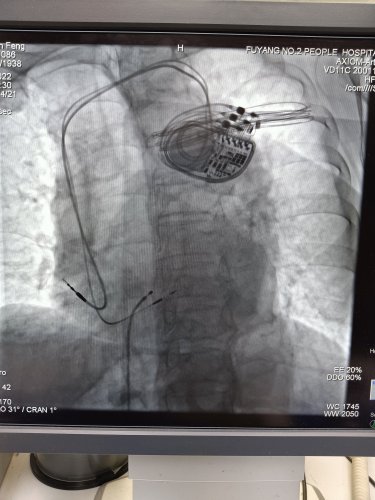

图5起搏器植入术中左束支区域位置的选择